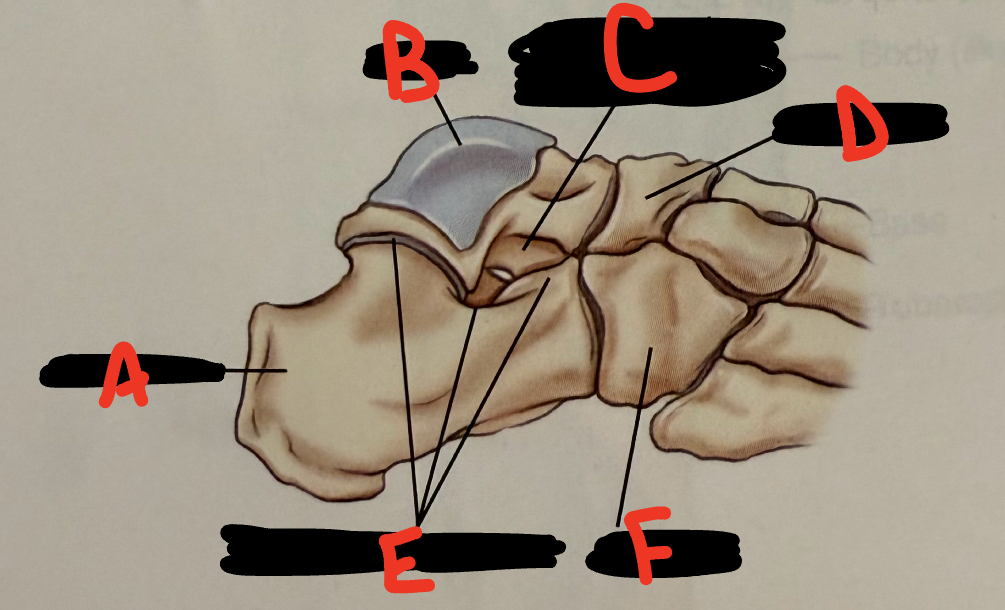

anterior tubercle

5

New cards

<p>E</p>

E

talus

6

<p>A</p>

A

fibula

7

<p>B</p>

B